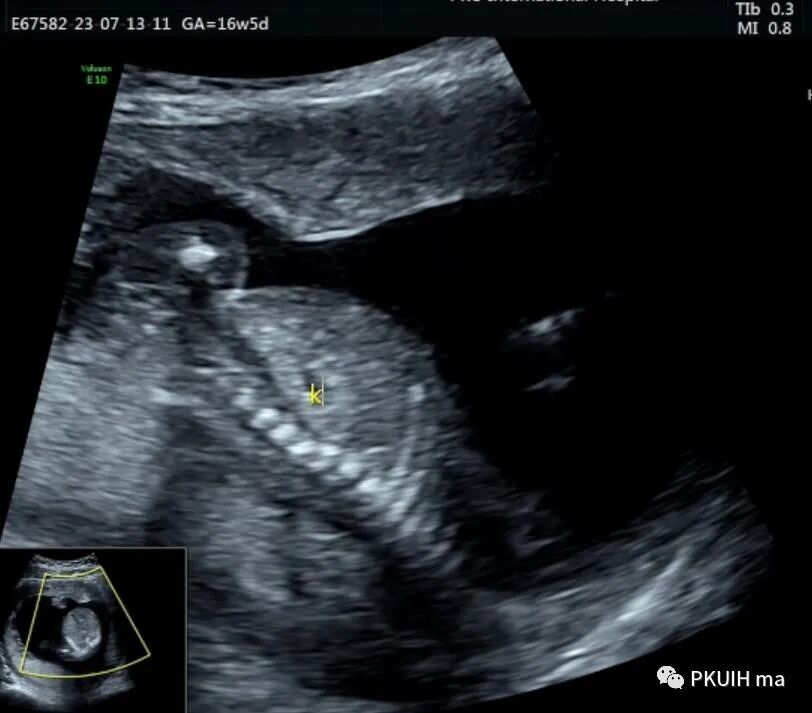

胎儿中腹部见一囊性包块,大小约1.2x1.0x0.8cm,边界清,形态规则,内透声好。囊肿位于脊柱前方、胆囊后方、门静脉窦旁,与后肾接近

仔细观察囊肿壁好像不完整,周边见微小管道回声与囊肿相通

CDFI:囊肿内未见明显血流信号。

由于囊肿位于胆囊后方、肝下方、门静脉窦旁,随考虑为胆总管囊肿

本病可于中孕及晚孕期被发现,其超声特征为肝门区囊性包块,形状呈圆形或椭圆形,位于门静脉右前方,可对门脉造成压迫。如果显示囊性包块与胆囊相通,则有助于诊断,彩超一般内部无血流信号。